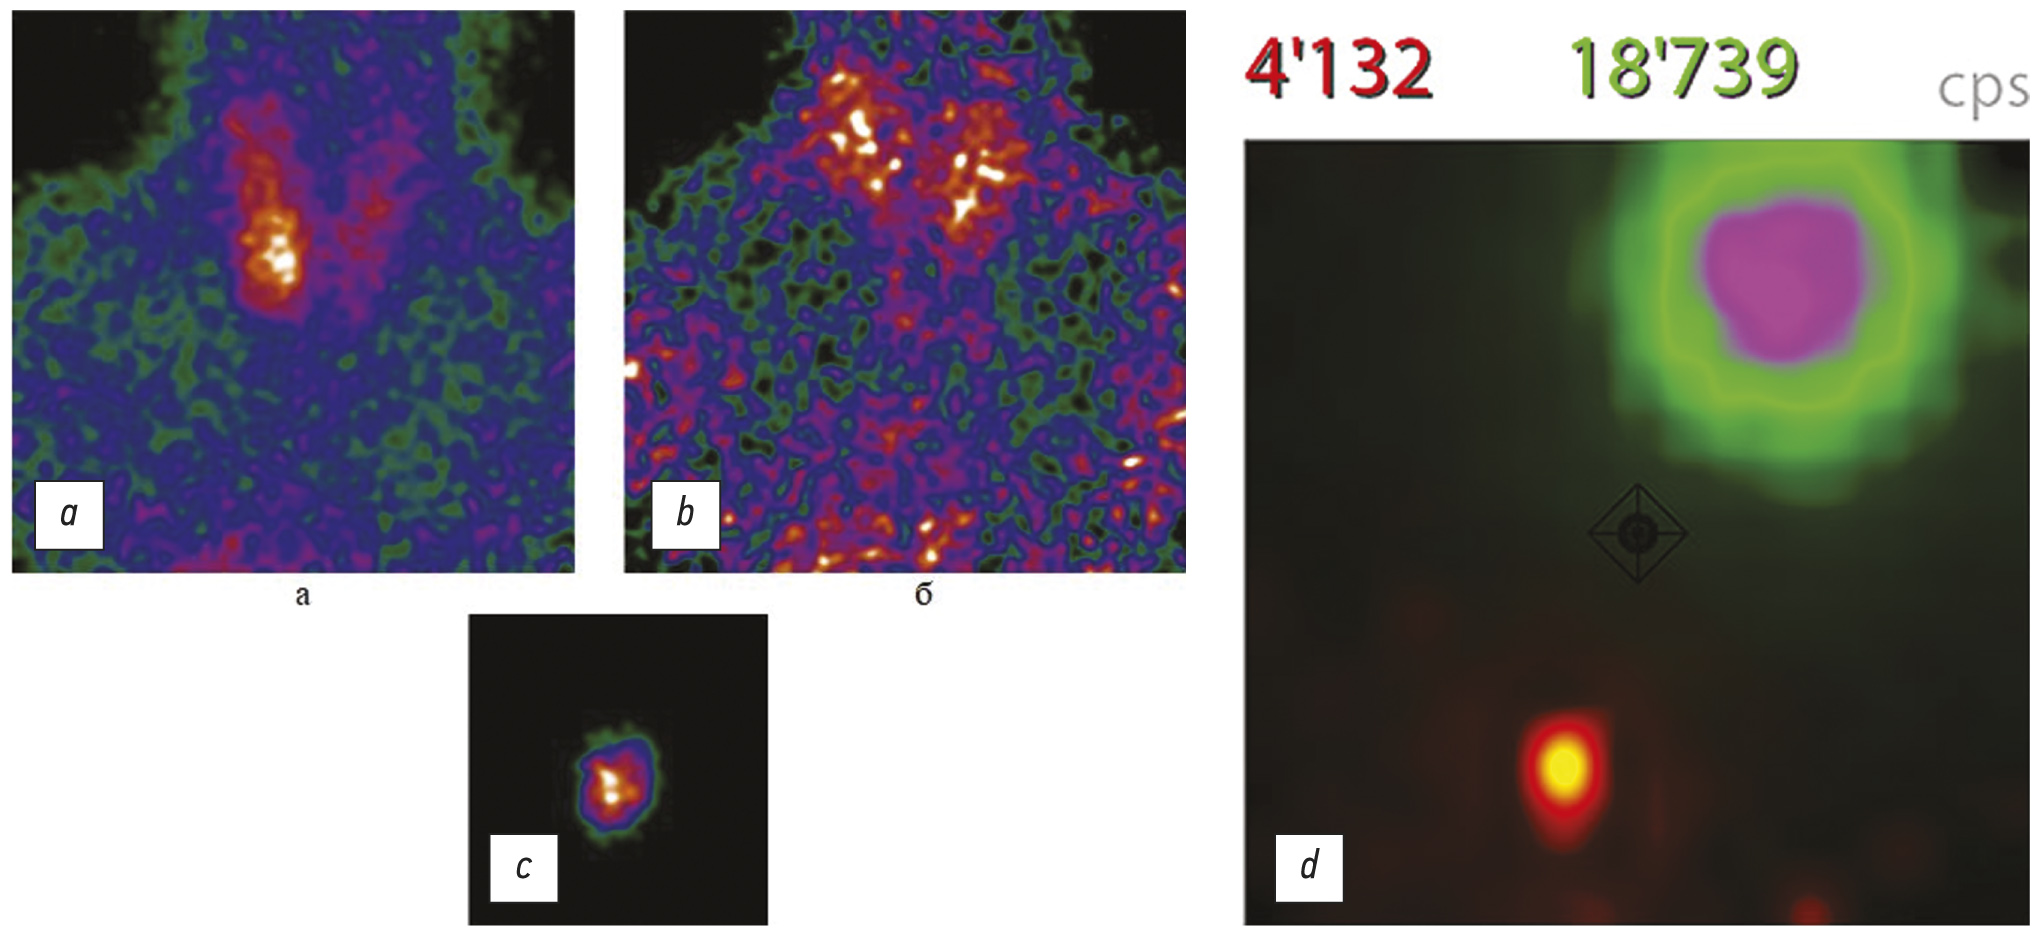

除超声外,还可以使用 99mTc-MIBI 进行单同位素双相闪烁扫描,或使用 99mTc-MIBI 和 99mTcO4(高锝酸盐)在 SPECT/CT 模式下进行双同位素闪烁扫描 [18, 19](图 3)。

图 3双同位素闪烁扫描:a - 99mTc-MIBI 闪烁扫描; b - 99mTc-TcO4 闪烁扫描。

HPT 局部诊断信息量最大的方法是使用 99mTc-MIBI 进行放射性核素诊断,尤其是在 SPECT/CT 模式下(图 4)。 平均而言,该方法的灵敏度达到 88%(阳性预测值为 96%)[20]。

图 4。使用 99mTc-MIBI(technetril)进行放射性核素研究:a - 两相平面闪烁扫描(早期和延迟扫描):甲状旁腺的形成在右叶(箭头)的投影中可视化,放射性药物的持续积累增加关于延迟扫描; b - 单光子发射计算机断层扫描,结合计算机断层扫描,99mTc-MIBI:在左叶下极(箭头)后面和向下形成甲状旁腺,积累放射性药物。

据文献报道,在 PGPT 患者中,99mTc-MIBI 研究的敏感性在 88% 的水平[21]。 诊断方法的组合给出了最好的结果。 因此,闪烁显像与 99mTc-MIBI 和超声相结合的灵敏度为 95%,而单独的超声诊断为 80%,放射性核素诊断为 87% [22]。